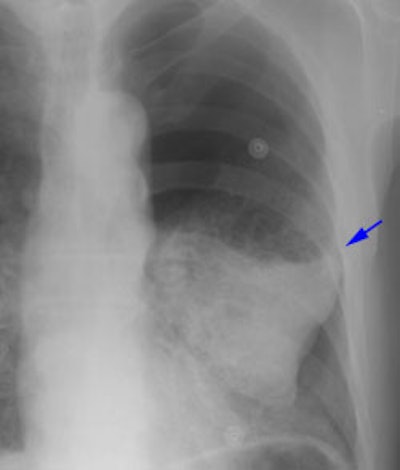

New Criterion for Determination of Pathologic Hilar Adenopathy

Example 1: This is an example of an N1 node in a patient with a lingular adenocarcinoma (left image). Although not pathologic by short axis size criteria, the lymphatic tissue in the left hilum has a convex border with the adjacent lung (white arrows). This node contained adenocarcinoma at histopathologic analysis. Some authors advocate using the presence of a convex margin of the interstitium with the lung parenchyma to indicate pathologic adenopathy to improve the sensitivity of CT for detecting hilar metastases [36].

NOTE: Click image to enlarge